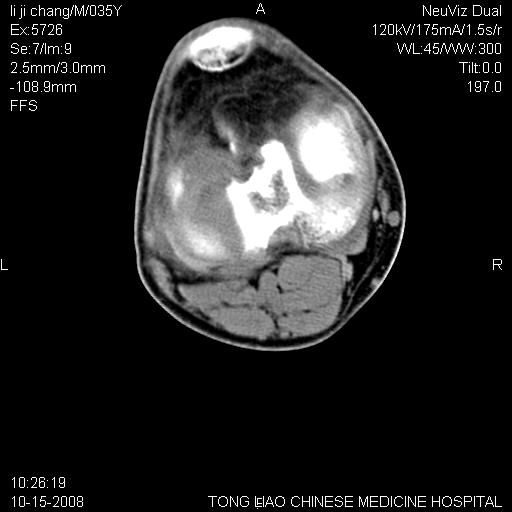

男,35岁,骨科诊断骨性关节炎。继往使用过激素,现股骨头坏死。膝关节病变,请会诊

一元论-----亦考虑为坏死

支持考虑无菌坏死

支持无菌坏死伴退行性骨关节病.

剥脱性骨软骨炎:是一种关节下软骨及软骨下骨缺血性坏死。

支持 无菌性坏死伴退行性骨关节病。